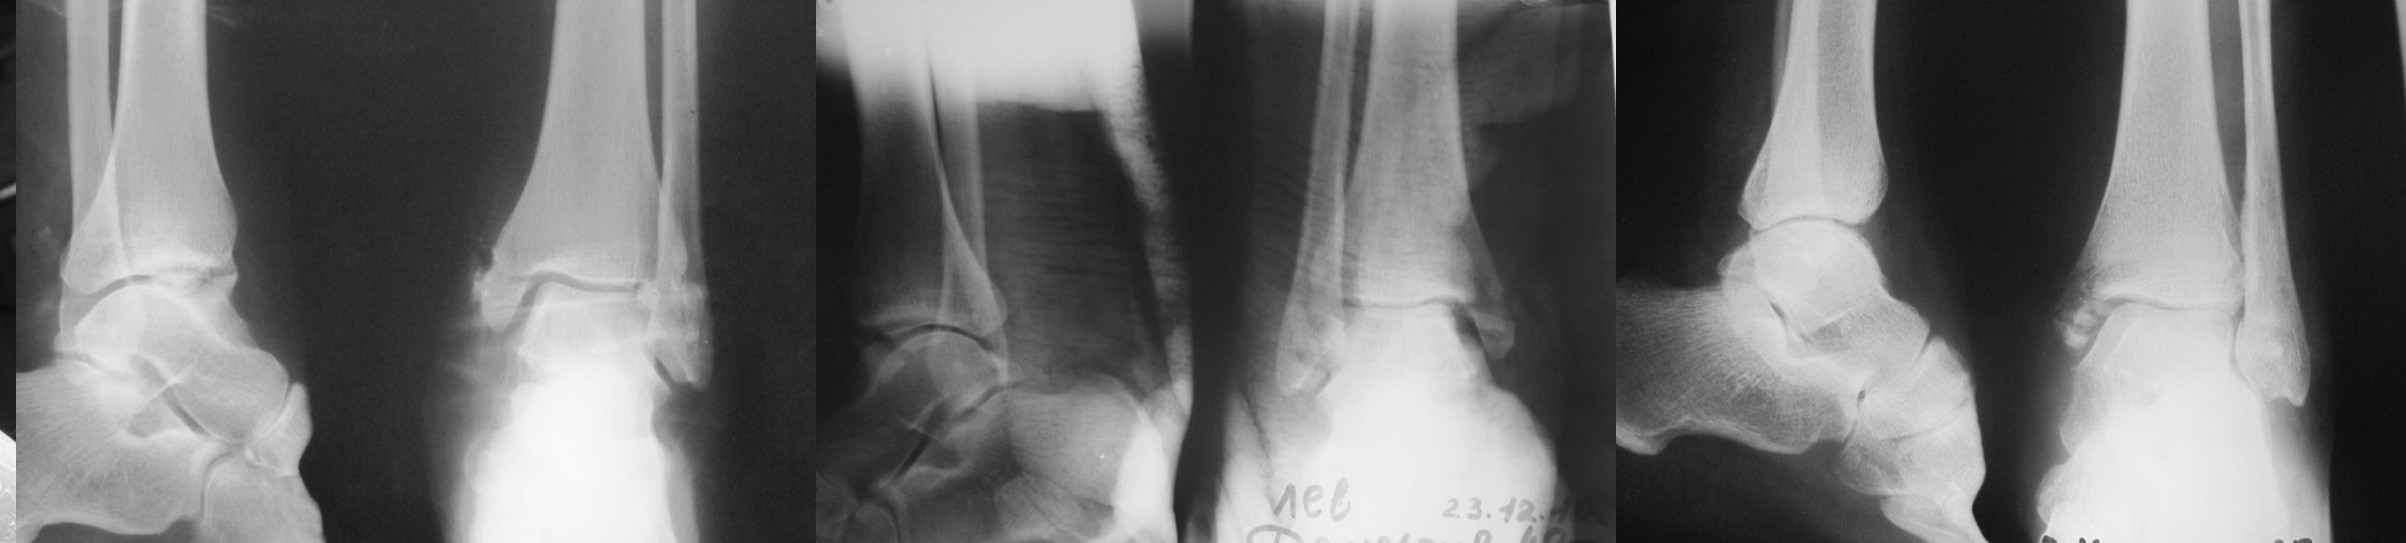

Травма в результате ДТП 1 января 2011г. открытый многооскольчатый перелом медиальной лодыжки левого голеностопного сустава со смещением. При поступлении в области медиальной лодыжки поперечная рана 5,0х1,0 см. сильно загрязнена, была выполнена ПХО. 05.01.2011г. сняты все швы по поводу нагноения раны, выполнена некрэктомия нежизнеспособных краев раны. На сегодня голеностопный сустав незначительно отечен, слегка болезнен при пальпации в области медиальной лодыжки. Температура тела нормальная, боли практически нет. Кровь спокойная. В области медиальной лодыжки имеется ранка округлой формы до 0,3 см., со скудным гнойным отделяемым (следы на салфетке после перевязки 1 раз в 2 дня). Посев из раны выполнить невозможно. На последних контрольных рентгенограммах признаки остеомиелита медиальной лодыжки? Помогите определиться с тактикой лечения: оперативное? Консервативное? С уважением Александр Белоконь!